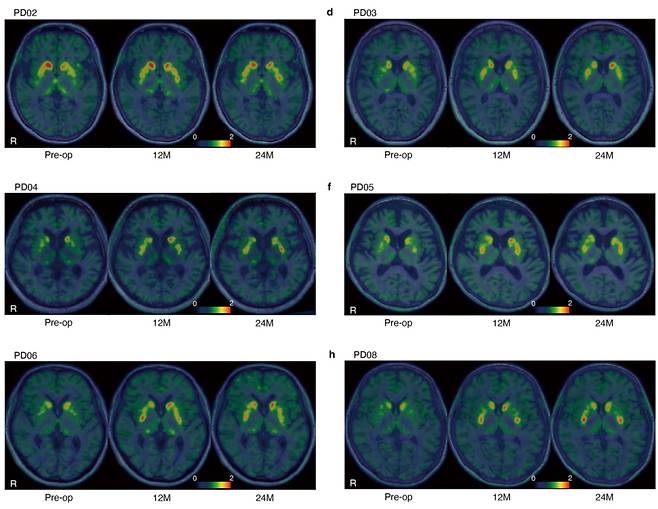

연구진은 유도만능줄기세포로 만든 도파민 신경전구세포를 환자 7명(저용량 3명·고용량 4명)의 뇌에 이식했다. 환자 7명을 추적한 결과 안전성에 문제가 없었다고 한다. 연구진은 “이식 세포가 과도하게 자라 종양이 되는 부작용이 나타나지 않았다”고 했다.

연구진은 또 환자 중 6명(저용량 2명·고용량 4명)을 대상으로 파킨슨병 치료 효과를 검사했다. 연구진은 “저용량·고용량 그룹 모두 뇌에서 도파민이 증가했다”면서 “특히 고용량 그룹에서 도파민이 많이 생성됐다”고 했다. 다만 두 연구진은 모두 “연구 기간이 짧았기 때문에 장기적인 연구가 필요하다”고 했다.